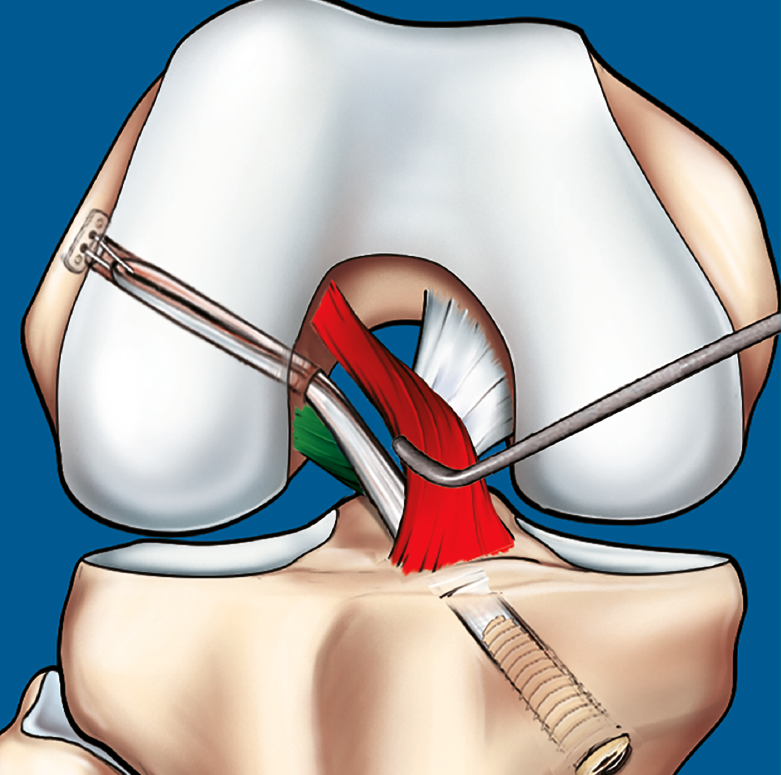

Figura 9. Esquema que ilustra el tratamiento con plastia de reconstrucción unifascicular posterolateral.

La reconstrucción selectiva del fascículo afectado sigue los principios básicos de la reconstrucción clásica anatómica del LCA (Figuras 9 y 10). Los autores realizan 3 portales: un portal anterolateral, lo más proximal posible con el fin de evitar la almohadilla grasa infrapatelar de Hoffa y tener una visión panorámica de toda la articulación; un portal AM alto y parapatelar, que utilizaremos como portal de visión y que nos va a permitir una mejor visualización de la huella anatómica femoral; y un portal AM accesorio, lateral al cóndilo femoral medial e inmediatamente superior al menisco interno, desde donde realizaremos el brocado del túnel femoral mediante técnica de manos libres(8). Otros autores recomiendan la realización del túnel femoral mediante técnica outside-in, considerando que ello facilita la realización del brocado femoral sin dañar las fibras del fascículo intacto(4).